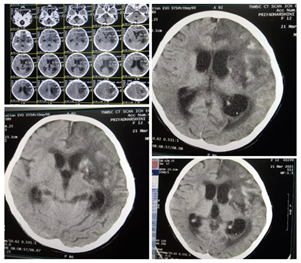

Unfractionated heparin was given at a bolus of 75 U/Kg bolus followed by 20 U/Kg/hr infusion. Child required inotropes for 13 days. On day 14, child developed right hemiparesis and CT brain revealed infarct involving left frontoparietal region [Figure 2]. She was extubated on day 20. MR angiogram revealed left MCA infarct. On day 21, oral nicoumalone at a dose of 0.2 mg/kg was started in addition to heparin under PT and aPTT monitoring. heparin was stopped on day 24. Nicoumalome and aspirin were continued. Repeat ECHO on day 27, showed no evidence of thrombi and ejection fraction was 60%. Protein C, S, Antithrombin III were normal. β2 glycoprotein [IgG & IgM] were negative. On day 37, anticoagulants were stopped as INR was prolonged. Subsequently, during hospital stay she developed malena and refractory hypotensive shock and seizures. She was reintubated. Repeat CT Brain showed subacute infarct of left frontoparietal region with hemorrhagic transformation [Figure 3]. Despite all efforts, child could not be saved.

Figure 3. CT brain revealing subacute hemorrhagic transformation of infarct of left frontoparietal region on Day 38.